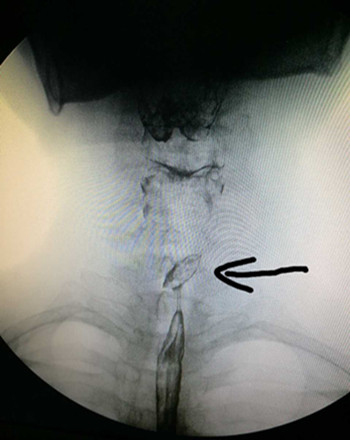

患者來我院就診時,咽痛嚴(yán)重,飲水時有哽噎感,4天來未進飲食,身體非常虛弱。遂抱著試一試的心態(tài)來到我院耳鼻咽喉科門診就診,張立剛副主任看過患者后經(jīng)過綜合評定,認(rèn)為我院已具備此例手術(shù)條件,門診遂以“食管異物”收住入院。入院后張立剛副主任立即組織安排手術(shù)前相關(guān)檢查事項,急查上消化道造影提示:食道(約第3胸椎水平)可見一橢圓形異物。尚規(guī)劃主治醫(yī)生立即給予積極完善相關(guān)檢查、補液、消腫,待患者基礎(chǔ)情況好轉(zhuǎn),能耐受手術(shù)后,急診在全身麻醉下行食管內(nèi)異物取除術(shù),用硬質(zhì)食管鏡直視下發(fā)現(xiàn)棗核兩端還是橫向扎在食道壁,此處離主動脈弓只有不到2cm,稍有不慎即可損傷主動脈造成無法控制的大出血,或者引起食道穿孔,與術(shù)前評估情況沒有差異。張立剛副主任沉著冷靜,尚規(guī)劃醫(yī)生一絲不茍,在兩人默契配合下,順利將棗核取出。術(shù)后患者在耳鼻咽喉科醫(yī)護團隊的細心治療與護理下于迅速康復(fù)出院。此例經(jīng)硬質(zhì)食道鏡成功取異物病例填補了我院硬質(zhì)食道鏡取除食道異物的空白。